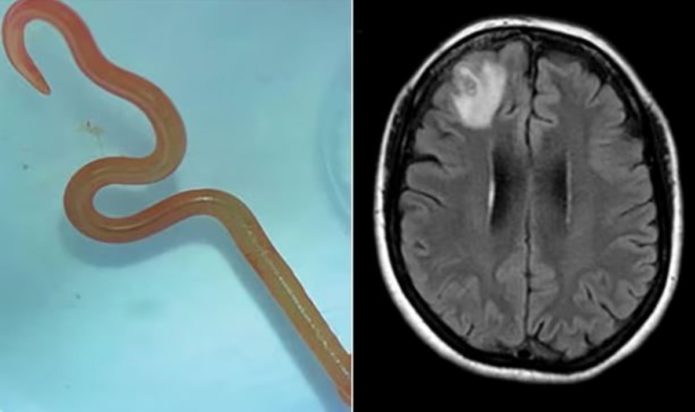

Σοκαρισμένοι ήταν οι γιατροί μίας κλινικής στην Αυστραλία όταν αφαίρεσαν από τον εγκέφαλο μίας 64χρονης γυναίκας ένα ζωντανό σκουλήκι μήκους 8 εκατοστών.

Η περιπέτεια υγείας της γυναίκας ξεκίνησε στα τέλη του 2021 όταν επί 3 εβδομάδες εισήχθη στο νοσοκομείο με πυρετό, πόνο στην κοιλιά, διάρροια, βήχα και νυχτερινές εφιδρώσεις. Έως το 2022 η γυναίκα παραπονέθηκε ότι ξεχνούσε συχνά και είχε συμπτώματα κατάθλιψης. Τότε οι γιατροί την υπέβαλαν σε μαγνητική τομογραφία και διαπίστωσαν ανωμαλίες στον εγκέφαλο της. Αποφάσισαν να την εγχειρίσουν και έμειναν άφωνοι όταν εντόπισαν το σκουλήκι.

Οι γιατροί του νοσοκομείου προσπάθησαν να ταυτοποιήσουν το σκουλήκι προκειμένου να βοηθήσουν την ανάρρωση της 64χρονης. Έτσι το έστειλαν σε εξειδικευμένο εργαστήριο για παράσιτα. Οι επιστήμονες του εργαστηρίου τους ενημέρωσαν ότι το σκουλήκι είναι το Ophidascaris robertsi.